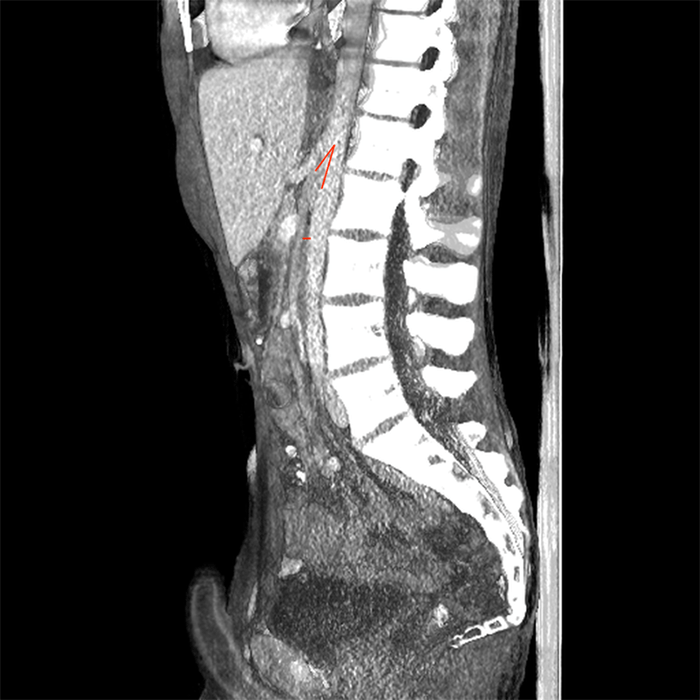

A healthy 16-year-old male with no prior surgical or psychiatric history presented with five days of worsening abdominal pain, emesis, and absence of bowel function after ingesting approximately 12 ounces of popcorn kernels. The patient reported that he had been given a large serving of popcorn at a movie theater had eaten the kernels because he did not want to be wasteful and was hungry; the event was witnessed and corroborated by his parents. On exam, the patient was hemodynamically normal with a non-distended abdomen and diffuse tenderness without peritonitis. His body mass index was 18.84 kg/m2. Laboratory evaluation including complete blood count, comprehensive metabolic panel, and urinalysis were unremarkable. A CT scan with intravenous contrast demonstrated severe dilation of the proximal duodenum with an acute transition point associated with a 20.5˚ angle between the superior mesenteric artery and the aorta and aortomesenteric distance of 3.3 mm, indicative of superior mesenteric artery syndrome (Figure 1 and Figure 2). Multiple small radiopaque objects filled the duodenum and distal stomach, which were confirmed to be popcorn kernels in a separate CT scan (Figure 3).

Figure 2. CT with intravenous contrast of the abdomen and pelvis. A sagittal reconstruction demonstrates a narrowed aortomesenteric angle measuring 20.5˚ and reduced aortomesenteric distance measuring 3.3mm, both marked.